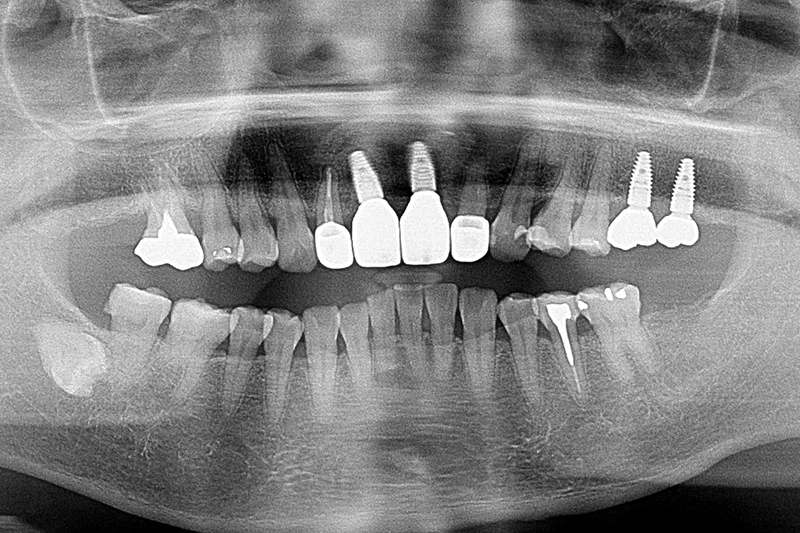

初診環口X光片檢測可見植體的角度位置都不理想,齒槽骨有吸收的現象。建議患者先接受牙周病的第一階段治療,進行感染控制

環口X光片術前

環口x光片術後

根尖X光片術前

根尖x光片術後